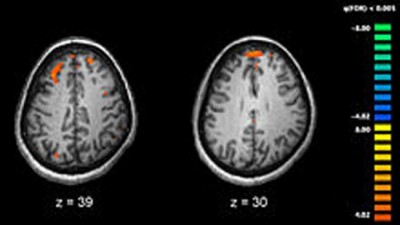

New York, Feb 21 (IBNS): The human brain largely remains a black box: How the network of fast-moving electrical signals turns into thought, movement and disease remains poorly understood.